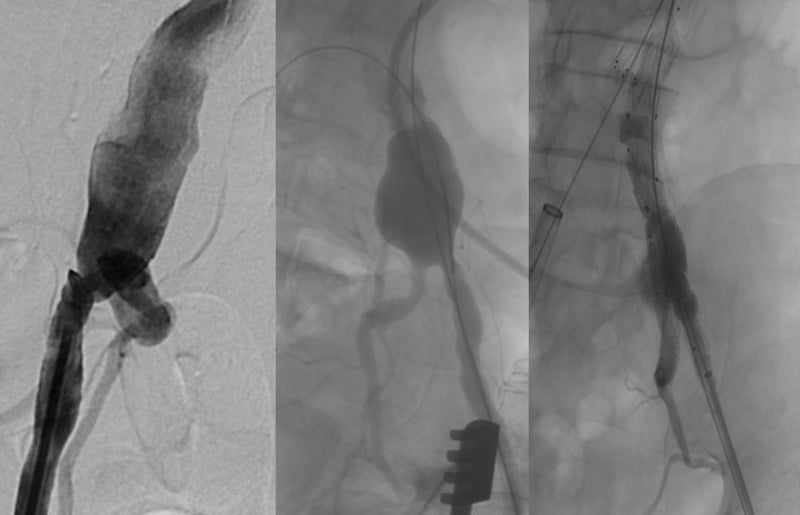

Step 1: TEVAR

Step 2: SMA and LRA stenting

(30 days after step 1)

Step 3: bilateral iliac branch

(45 days after step 2)

Step 4:

(30 days after step 3)

- RRA stenting

- Celiac trunk

Cannulation

Failure

↓

Branch

Embolisation